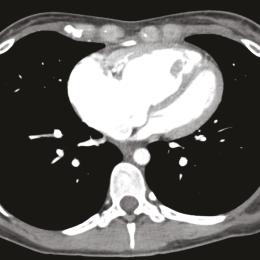

Hypertension pulmonaire

L’hypertension pulmonaire (HTP) se définit par une élévation permanente des pressions artérielles pulmonaires, qui peut être la conséquence d’une maladie vasculaire pulmonaire (HTP précapillaire), d’une augmentation passive des pressions liée à une cardiopathie gauche (HTP post-capillaire…